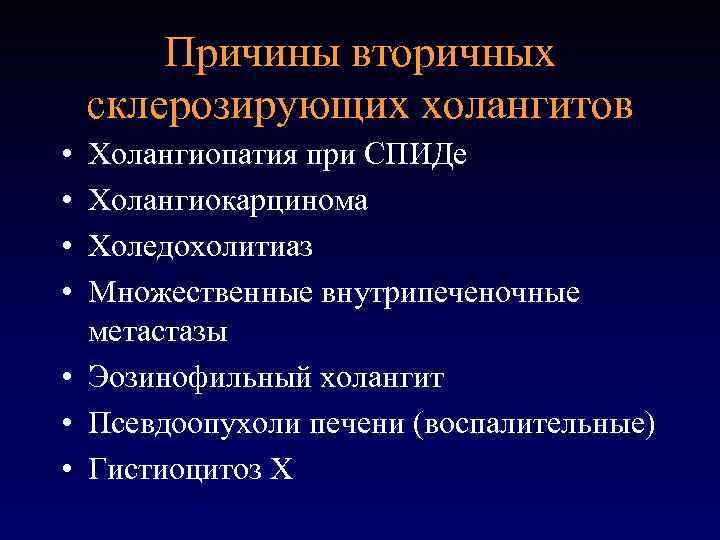

Фотографии и изображения, связанные с симптомами первичного склерозирующего холангита